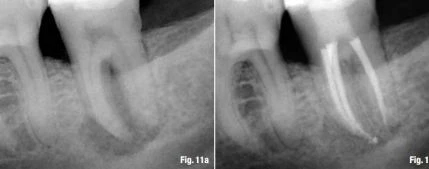

Nếu điểm thắt chóp cách chóp răng 0.5 mm thì 66% là tất cả các dụng cụ đã đi quá nó. Khi file còn cách chóp trên X-quang thì sự thật là nó gần với lỗ chóp hơn so với hình ảnh xuất hiện trên X-quang. Chiều dài làm việc trên X-quang chấm dứt cách chóp trên X-quang từ 0 đến 2 mm nên dụng cụ dễ đi quá chóp mà chúng ta không hề biết, và điều này xảy ra thường xuyên hơn mong đợi. Hình ảnh từ 16a đến 17b là để minh họa những sai lầm trong việc quyết định WL, nó có thể được cải thiện để đạt được thành công cuối cùng.

Quyết định chiều dài làm việc và cách xác định điểm chóp cuối cùng  3

Hình 16a & b: Tình huống lâm sàng với dụng cụ quá chóp (a), sau đó được cải thiện lại bằng việc trám bít ống tủy cách chóp trên X-quang khoảng 0.8 mm.

Quyết định chiều dài làm việc và cách xác định điểm chóp cuối cùng  6

Hình 17a & b: Cải thiện lỗi sai khi quyết định WL (a) và kết quả cuối cùng ít nhiều thành công hơn (b).